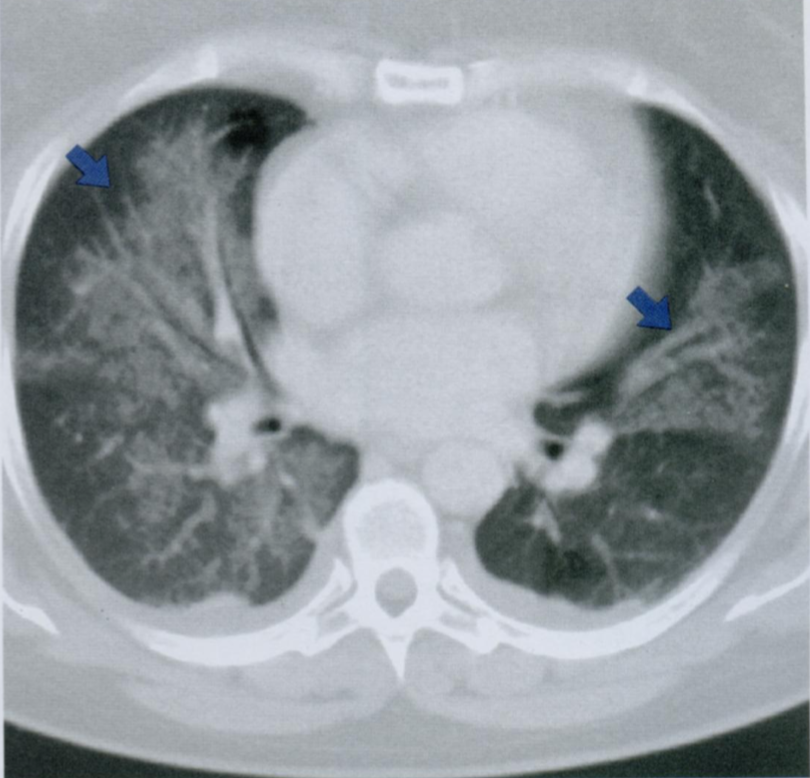

22

Q

КТ органов грудной клетки высокого разрешения.

Что Вы видите на данном КТ снимке? Постарайтесь вспомнить и назвать все анатомические структуры.

Что отмечено стрелками?

При хронических и прогрессирующих заболеваниях, когда ткань легкого становится более плотной из-за рубцевания и фиброза, податливость и вентиляция легкого уменьшается.

В результате формируется высокое стояние диафрагмы, кистозные изменения в виде “сот” и эмфизема. На ранних стадиях заболевания, когда еще нет признаков поражения на Rx, можно увидеть изменения на спирометрии и КТВР.

A

Стрелками отмечен симптом матового стекла, напоминающий воспалительную экссудацию или неопластическую инфильтрацию.

26 - грудные позвонки

24 - грудина

2 - правое предсердие

7 - восходящая аорта

9 - легочный ствол

3 - левое предсердие

10 - сосуды легких

8 - нисходящая аорта

15 - непарная вена

16 - пищевод